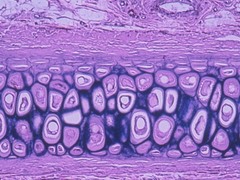

hyaline cartilage

Front

Most common type of cartilage; it is found on the ends of long bones, ribs, and nose